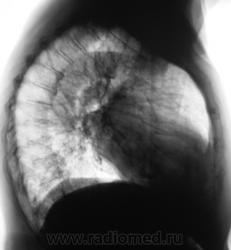

- https://radiomed.ru/sites/default/files/styles/case_slider_image/public/user/12/33.Pen_.JPG?itok=JBHzd3lX

Задача наша будет легче, если укажете это «нечто» в боковой проекции. Ведь всё, что перечислила Ваша Эрудиция здесь и ранее – трёхмерные объекты, отнюдь не плоские. Не так ли?

Образование средостения. Вопрос в том, где оно на боковой?! Наслаивается на тень сердца? Исходит из сердечной сумки? Барий не давали?